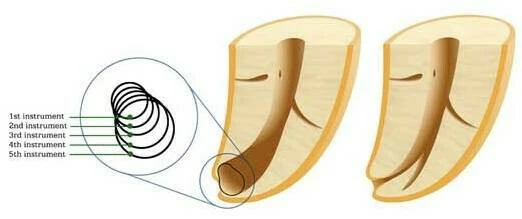

Trong hình bên dưới có thể thấy: trâm số nhỏ có thể uốn cong theo hình dạng ban đầu của ống tủy, sau khi nong rộng ống tủy với trâm số lớn hơn thì ống tủy có nguy cơ bị dịch chuyển.

Trong hình minh họa bên dưới: Với răng cối lớn với ống tủy cong nhiều.

- (a) Phim X-quang ban đầu với trâm số #15, độ cong 42 độ.

- (b) Phim X-quang sau khi sửa soạn bằng trâm nickel-titanium số #40, độ cong 35 độ.

Như vậy kết quả của việc sửa soạn chỉ làm ống tủy bị dịch chuyển nhẹ về phía ngoài của đoạn cong mà thôi.